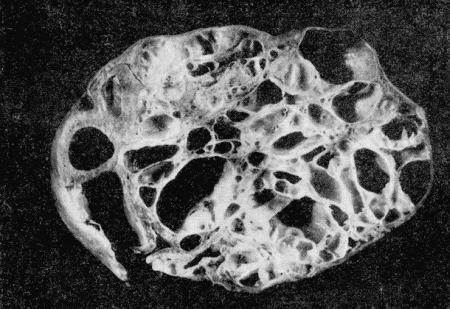

Опухоли обычно имеют вид единичных, ограниченных шаровидных образований и могут достигать больших размеров. Диффузно растущие опухоли у сук встречаются очень редко. Почти во всех случаях в опухолях обнаруживают кистевидные полости (рис. 156–157). Эти полости представляют собой результат дистрофических процессов, развивающихся в ткани опухоли. Наиболее часто образуется некроз и распад тканей в круглоклеточных и особенно в полиморфноклеточных саркомах. В результате некроза, связанного с жировой дистрофией и ядерным распадом, и образуются кистевидные полости. Причиной некроза может быть кровяной стаз и тромбозы сосудов.